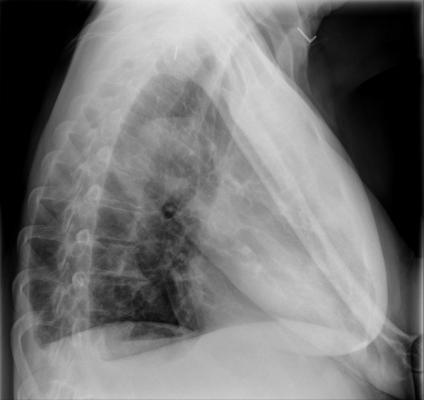

While imaging plays a pivotal role in the diagnosis and management of tuberculosis (TB), access to radiology is often limited in the developing countries where TB is most prevalent. Hoping to bridge that gap, Lakhani and colleague Baskaran Sundaram, M.D., also from TJUH, investigated the efficacy of an automated method for detecting TB on chest radiographs. Specifically, the researchers used deep learning, a type of artificial intelligence (AI) using pre-trained deep convolutional neural networks (DCNNs), to identify TB on chest X-rays. The results of the research were promising.

For the study, Lakhani and Sundaram obtained 1,007 X-rays of patients with and without active TB, consisting of multiple chest X-ray datasets from the National Institutes of Health, the Belarus Tuberculosis Portal and TJUH. The datasets were split into training (68 percent), validation (17.1 percent) and test (14.9 percent).

The cases were used to train two different DCNN models – AlexNet and GoogLeNet – which learned from TB-positive and TB-negative X-rays. The models’ accuracy was tested on 150 cases that were excluded from the training and validation datasets. The best performing AI model was a combination of the AlexNet and GoogLeNet, with a net accuracy of 96 percent.